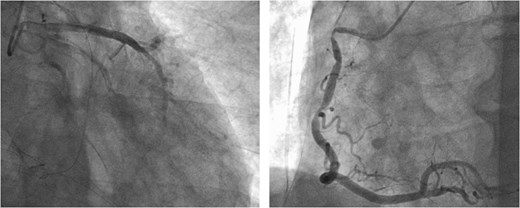

Following closure of the PA and cessation of cardiopulmonary bypass, ST-segment elevation was observed, accompanied by a deterioration in the patient's hemodynamics. Consequently, an intra-aortic balloon pump (IABP) was inserted via the right femoral artery and coronary angiography (CAG) revealed spasms along the entire length of the RCA and obtuse marginal artery (Fig. 5). These spasms improved generally after administration of nitroglycerin (Fig. 6). However, ventricular fibrillation was provoked, leading to unstable hemodynamics. Therefore, veno-arterial extracorporeal membrane oxygenation was initiated, and the surgery was concluded. Extracorporeal membrane oxygenation (ECMO) and IABP were withdrawn 4 days and 5 days after surgery, respectively. The patient's postoperative course was good, and he left the hospital on post-operative day 20.

Intraoperative CAG revealing vasospasms along the entire length of the RCA and OM artery.